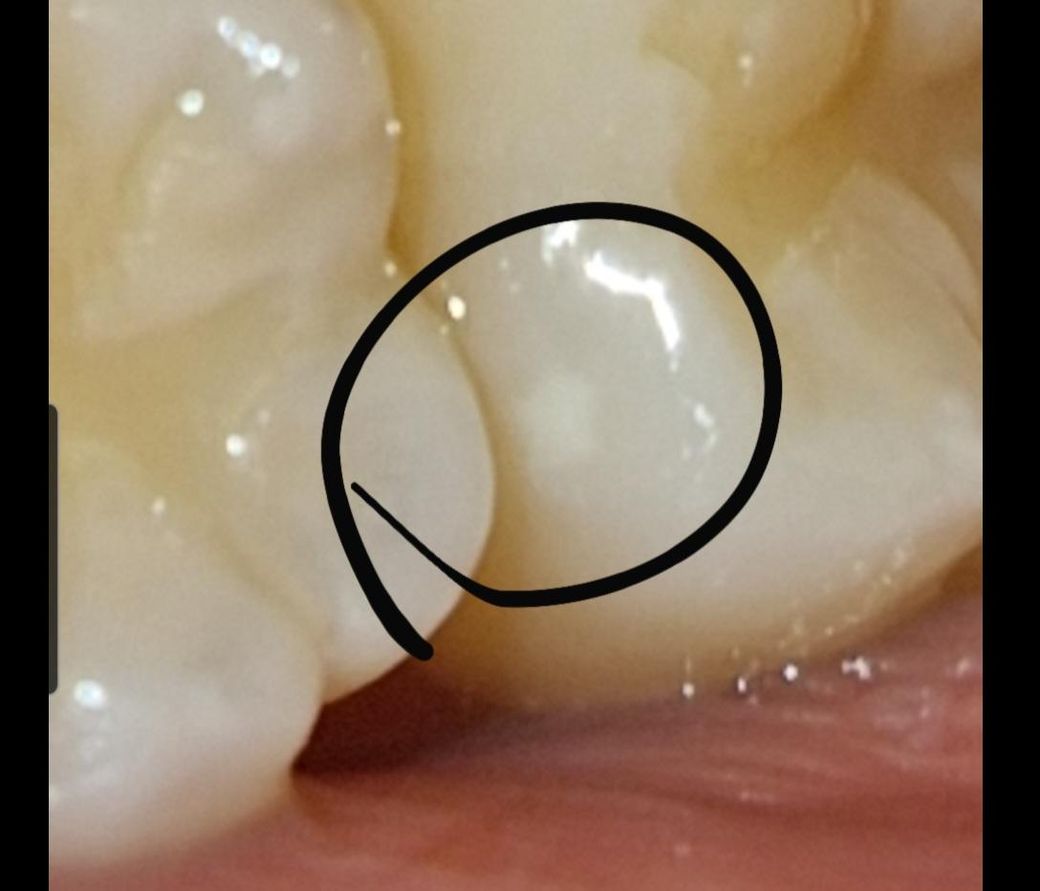

이빨에 하얀 반점같은게 생겼어요. 충치인가요?

이빨에 하얀 반점같은게 생긴것 같아요. 씹을때 통증같은건 없고 저번주 파노마라에서도 딱히 이상이 없었습니다. 충치인가요? 원인이 궁금해요

사진으로 봤을 경우에는 정확한 확인이 어려워 보입니다. 초기 충치의 경우에는 치아 표면이 하얗게 보이는 경우도 있습니다. 극히 초반에 충치라면 양치질을 잘 해주고 관리를 해준다며 축제가 더 진행되지 않는 경우도 있습니다.

초기 충치일 가능성도 있으나 만약에 해당 부분이 활택(매끈)하다면 선천적인 치아의 저강화(hypomineralization)일 가능성이 큽니다. 이러한 경우라면 치료를 급하게 하기 보다는 주기적으로 치과를 방문하여 추적 관찰하는 것이 좋으며 조금이라도 충치로 이어질 것 같다면 간단히 제거 후 레진으로 치료하는 것이 좋습니다.

사진에 보이는건 충치는 아니고 치아 표면이 탈회된걸로 큰 문제가 잇는건 아니니 너무 걱정하지마세요.

초기충치의 양상 중 하나인 백색반점(white spot)의 가능성이 있어보입니다. 불소 포함된 치약으로 양치해주시기 바랍니다.